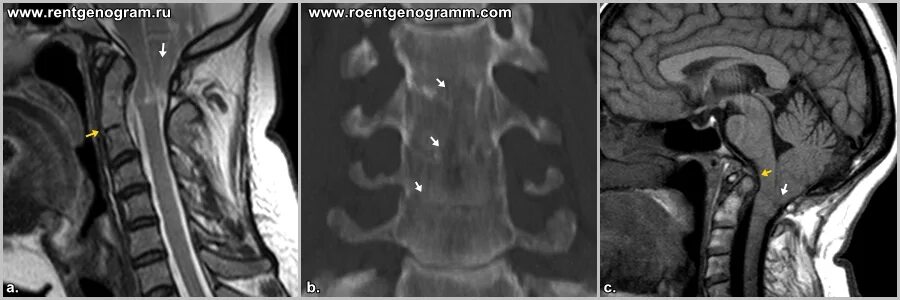

Код мкб арнольда киари